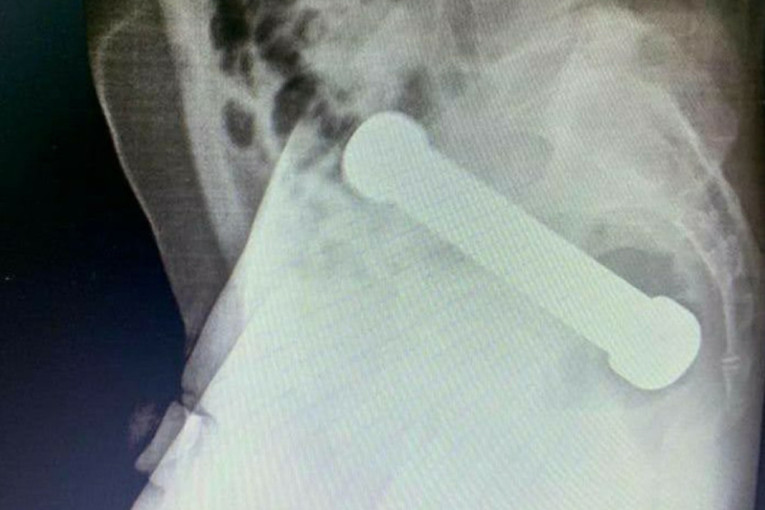

Pacijent je čekao najmanje 48 sati pre nego što je potražio medicinsku pomoć, a u međuvremenu je pokušavao da samostalno ukloni predmet. Kada su ga lekari pregledali, bio je klinički stabilan, ali su rendgenski snimci otkrili šokantnu činjenicu - u rektumu mu se zaglavio metalni teg težak čak dva kilograma.

Muškarac je priznao da je teg dužine 20 centimetara sam ubacio kroz analni otvor, ali se predmet zaglavio, što je prouzrokovalo jake bolove, mučninu i opstrukciju creva.